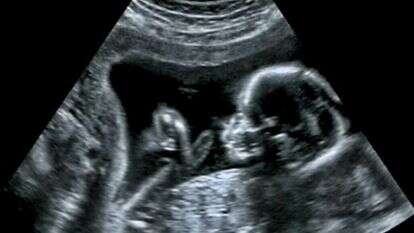

היפרדות שליה מוקדמת מוגדרת כהתנתקות - חלקית או מלאה - של השליה מדופן הרחם, המתרחשת לפני יציאת העובר מהרחם. כשליש מהדימומים במהלך חודשי ההיריון המתקדמים נובעים מהיפרדות. הסימנים להיפרדות יהיו בדרך כלל כאבי בטן ודימום רחמי.

התמונה הטיפוסית היא דימום וגינלי המלווה בכאבי בטן ובהתכווצויות של הרחם. האבחנה היא בבדיקה גינקולוגית, בה ניתן להתרשם מטונוס מוגבר של הרחם- רחם מתוח ופעימות לא סדירות של לב העובר. אם היפרדות השליה משמעותית אפשר לאבחן זאת בבדיקה אולטרסאונד. במקרים מסוימים יתכן מצב של דם שנאגר מאחורי השליה ואז נראה כאב בטן ובטן מתוח וכמובן שינויים בדופק העוברי. זה עלול להיות מסוכן מאד.